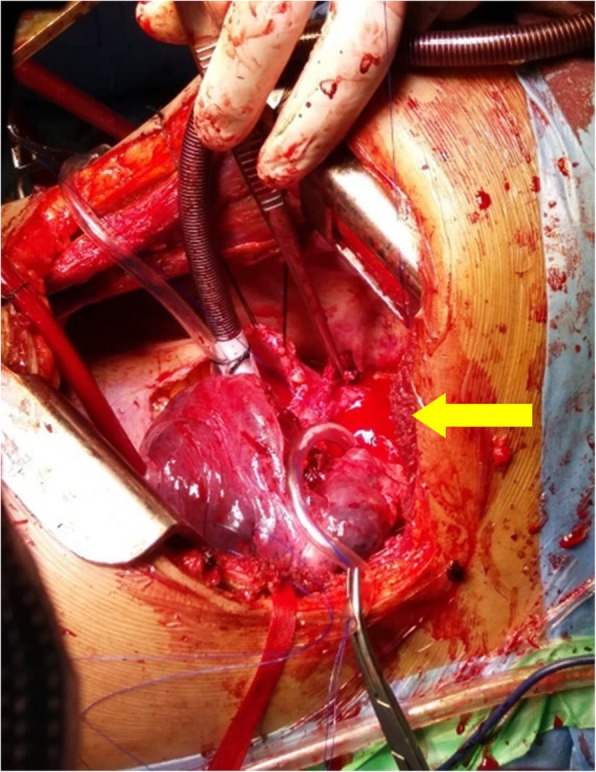

Fig. 3.

Intra-operative picture showing a ruptured aortic anreuysm (yellow arrow)

Subsequently, an urgent repair of the aneurysm was planned. Left posterolateral thoracotomy was performed and the large pseudo-aneurysm of the descending aorta from the origin of the subclavian artery was identified. The aneurysm was seen to have ruptured into the apical segment of left upper lobe leading to intermittent hemoptysis and was contained mainly from the thrombus.

With partial bypass via main pulmonary artery and distal aortic cannulation, proximal and distal control was obtained and the aneurysm was opened. The posterior wall of the pseudo-aneurysm was intact and the anterior wall was debrided. A bovine pericardial patch was used to repair the aortic defect; multiple plegetted sutures were also used to strengthen the repair. The patient was taken off bypass and after successful hemostasis, the chest was closed. Post operative course was un remarkable. The aortic wall, left lung tissue, and para-aortic lymph node samples were sent for histopathological analysis, bacterial, fungal and TB culture and sensitivity. They showed fibrocollagenous tissue fragments with necrotic inflammatory exudate and the lymph nodes showed reactive lymphoid hyperplasia. The cultures grew Enterobacter species sensitive to Amikacin, Meropenem and Imipenem, confirming the diagnosis of an infected aortic aneurysm. The patient was hence, prescribed IV Imipenem for 6 weeks. She continues to follow up in clinic and is in good health.